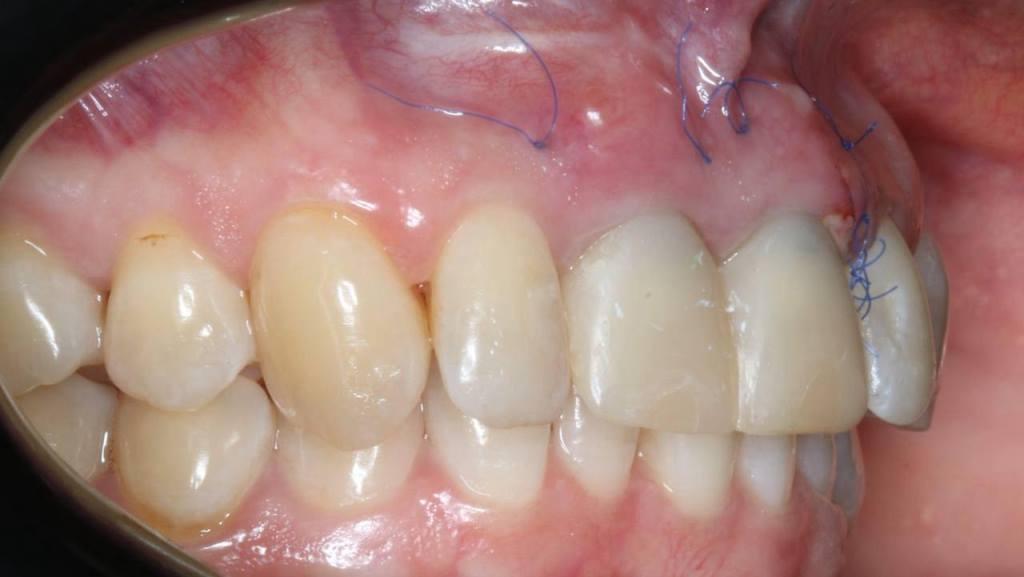

Фото 3, 4, 5.

Очень важно во фронтальном отделе корректное параллельное расположение имплантатов во всех трех плоскостях.

Фото 6, 7.

Зубо-альвеолярная реконструкция подразумевает немедленное протезирование. Необходимо во время операции получить достаточную стабильность имплантатов, чтобы ортопед смог сразу изготовить временные коронки, которые будут поддерживать контур мягких тканей. Пациент уходит из клиники с зубами.